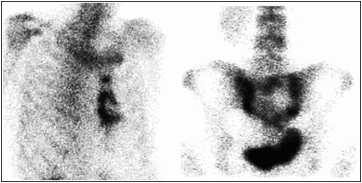

なお、骨転移は、溶骨を主体としたもの、造骨を主体としたもの、その混合型という分類の他にも、臨床上見つけにくい形の骨転移;骨変化のない 骨梁間型(骨髄転移)がありますが、FDG-PETで良く発見されるようになりました。 この形の骨転移は、MRIもしくはFDG−PETでは見えますが、CTや骨シンチでは検出できません。

乳がんの骨転移では、溶骨の要素が多く、診断法は、従来用いられてきた骨シンチグラフィからFDG-PET/CTへと徐々に変化しています。我々は、この骨移転移診断法の変化に対応する方法の研究を行なっています。

また、少し機序は異なりますが骨転移巣への局所放射線療法があります。骨シンチグラフィは、BPにガンマ線を出す核種を標識したものですが、骨シンチグラフィの画像を見ると骨転移の部分に非常に大量のBPが集積している場合があります。ガンマ線をベータ線に替えることにより、悪い所だけに対する放射線療法が出来ます。ストロンチウム-89を骨転移患者さん(この場合、骨シンチグラフィで転移の部分にたくさんの放射能があることを確認した後)に投与することで、骨転移に対する特異的な治療が可能です。さらに、骨転移の治療にα線核種も使用されるようになってきました。当施設でも、去勢抵抗性前立腺癌骨転移の患者さんにα線核種であるRa-223が治療法として用いられています。